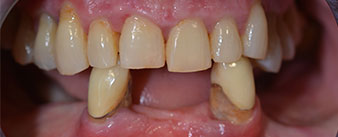

The 64-year-old patient presented with residual dentition of teeth 38, 33 and 43 and a clasp denture in the mandible (Fig. 1 and 2).

Fig. 2